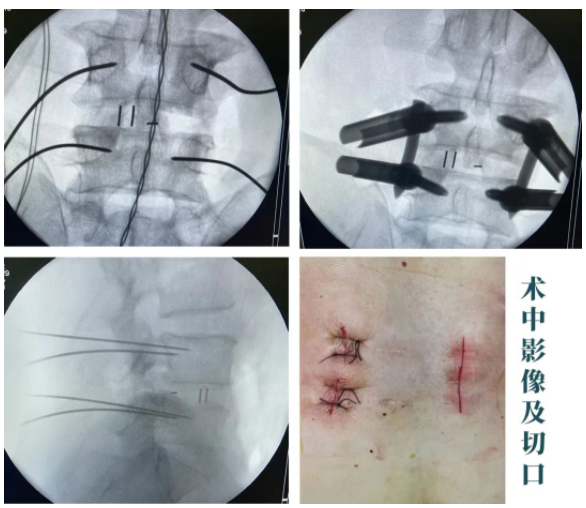

随后,sararz脊柱外科尚军、孟磊手术团队为王先生进行了在智能骨科机器人+3D裸眼显微镜辅助下,经皮腰椎后路减压+内固定+椎间融合术(L4/5)。

术中